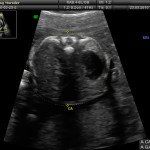

L’ecografia è una tecnica che consente di vedere gli organi del nostro corpo con l’utilizzo di onde sonore ad alta frequenza (ultrasuoni, non udibili dall’orecchio umano) che attraversano i tessuti. La sonda ecografica invia impulsi di onde sonore nel corpo. Quando le onde sonore arrivano al feto mandano degli echi: tali echi (o onde di ritorno) sono trasformati in immagini sul monitor dell’ecografo. Con l’ecografia è quindi possibile osservare in modo dettagliato il feto.

Le ragioni più comuni per cui si esegue una ecografia in gravidanza sono: determinare il numero degli embrioni o dei feti, visualizzare l’attività cardiaca fetale, determinare l’epoca di gravidanza, valutare l’anatomia e la crescita fetale, determinare la posizione del feto e della placenta

Nei primi mesi di gravidanza, con la misura della lunghezza del feto, è possibile valutare se lo sviluppo corrisponde all’epoca di gravidanza valutata in base alla data dell’ultima mestruazione, il numero dei feti e la presenza dell’attività cardiaca.

Dal secondo trimestre si misurano altre parti fetali, ed i valori di tali misure vengono confrontati con quelli delle curve di riferimento. Si può così valutare la normalità o meno della crescita fetale. Inoltre periodo si visualizzano la sede di inserzione placentare e la quantità di liquido amniotico.

- E’ possibile rilevare con l’ecografia anomalie fetali maggiori?

La possibilità di rilevare un’anomalia maggiore dipende dalla sua entità, dalla posizione del feto in utero, dalla quantità di liquido amniotico e dallo spessore della parete addominale materna; perciò è possibile che talune anomalie fetali possano non essere rilevate all’esame ecografico. Inoltre alcune malformazioni si manifestano tardivamente (al 7°- 9° mese) e perciò non sono visualizzabili in esami precoci. L’esperienza finora acquisita suggerisce che un esame ecografico routinario, non mirato, consente di identificare dal 30 al 70% delle malformazioni maggiori. Non è compito dell’ecografia la rilevazione delle cosiddette anomalie minori (Linee Guida SIEOG 2006).

A fianco alla più tradizionale ecografia eseguita per via transaddominale, risulta particolarmente utile nell’esame ecografico ostetrico e ginecologico la via di accesso transvaginale.

Con questa metodica, utilizzando delle sonde ecografiche appositamente predisposte (per forma e dimensione, e per frequenza di emissione degli ultrasuoni) è possibile controllare la gravidanza nel primo trimestre con una qualità e definizione d’ immagine nettamente superiori a quanto possibile per via transaddominale.

Con l’ecografia transvaginale è possibile vedere dopo circa 3 settimane dal concepimento la camera gestazionale nella cavità uterina. Successivamente è possibile visualizzare l’embrione (3-5 mm.) a circa 6 settimane dall’ultima mestruazione (4 settimane dal concepimento) ed a questo periodo è già visibile l’attività cardiaca fetale Anche i primi dettagli sulla morfologia fetale (polo cefalico, abbozzi degli arti) sono visualizzabili più precocemente con l’ecografia transvaginale, risultando essi visibili intorno a 8-9 settimane.